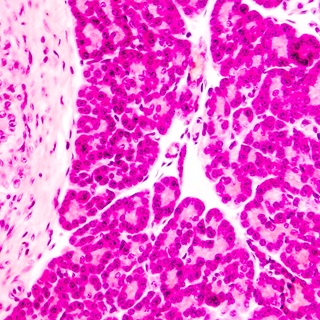

In type 1 diabetes, the immune system mistakenly attacks insulin-producing cells in the pancreas called beta cells. This reduces insulin production over time, causing blood sugar levels to rise. Eventually, the patient must take supplemental insulin for life.